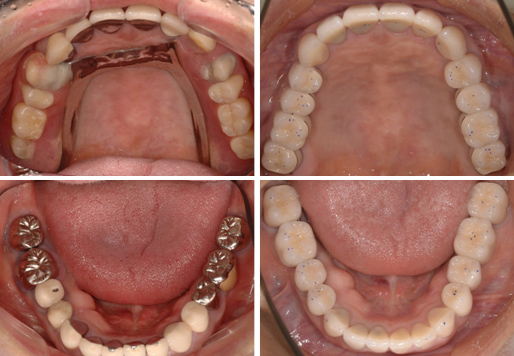

上下顎28本単冠セラミック修復(インプラント上顎6本、下顎3本)

右写真の歯の細かい点は、咬み合わさっている部位を印記して、精密に調整した状態です。入れ歯のわずらわしさからインプラントに代わり,審美性・機能性とも回復しました。

クインテッセンス出版社・デンタルインプラントロジー2018年第5巻掲載